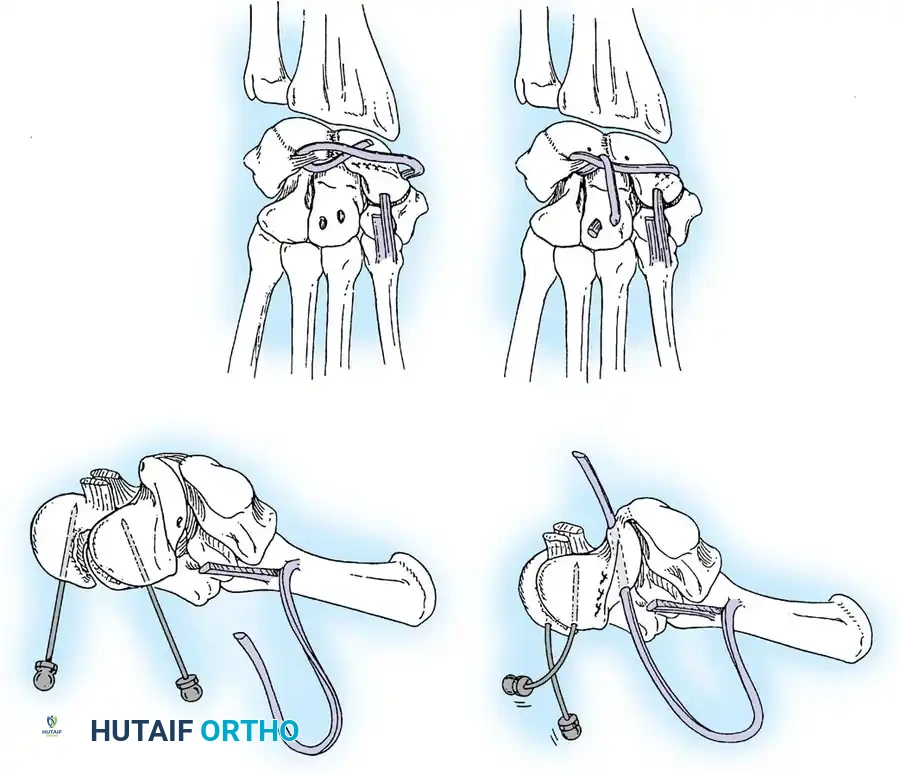

A rigid fusion column must be established through the carpus to the metacarpal, coinciding precisely with plate placement. The fundamental principle is that all joints spanned directly by the plate must be fused; adjacent joints (such as the carpometacarpal joints of the index and middle fingers) can be included if degenerative changes are present.

- Plate Application: A 3.5-mm dynamic compression plate (DCP) is applied from distal to proximal. The plate is specifically contoured to provide 10 to 15 degrees of wrist extension. The plate spans the local radial bone graft augmentation, ensuring rigid compression across the fusion mass.

Surgical Warning: Ensure the distal screws engage the dense diaphyseal bone of the third metacarpal without penetrating the palmar cortex, which could tether the flexor tendons. The thickness of the plate distally must be accommodated by adequate soft tissue closure to prevent extensor tendon irritation.